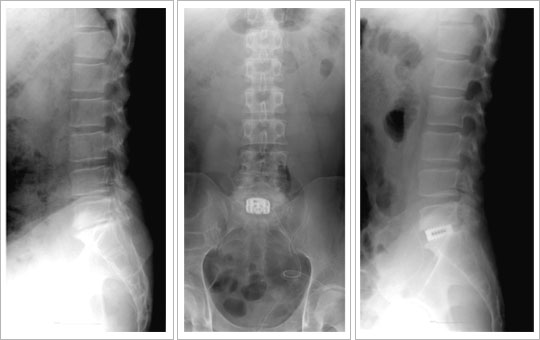

: ôÃßÀÇ Áúȯ Áï °ñÀý, Á¾¾ç, °¨¿° µîÀÌ Ã´Ãß Àü¹æºÎ¸¦ ½ÉÇÏ°Ô Ä§ÀÔÇÏ¿© ½Å°æ

ºÒ¾ÈÁ¤¼ºÀÌ ÀÖÀ» °æ¿ì¿¡ ÀûÀÀÀÌ µÇ¸ç, º¯¼ºÀÌ ½ÉÇÑ ÅðÇ༺ Ãß°£ÆÇ¿¡¼

Á¦°Å°¡ ÇÊ¿äÇÑ °æ¿ì¿¡ Àü¹æ°¨¾Ð¼ú ¹× À¯ÇÕ¼úÀ» ½ÃÇàÇÏ°Ô µË´Ï´Ù.